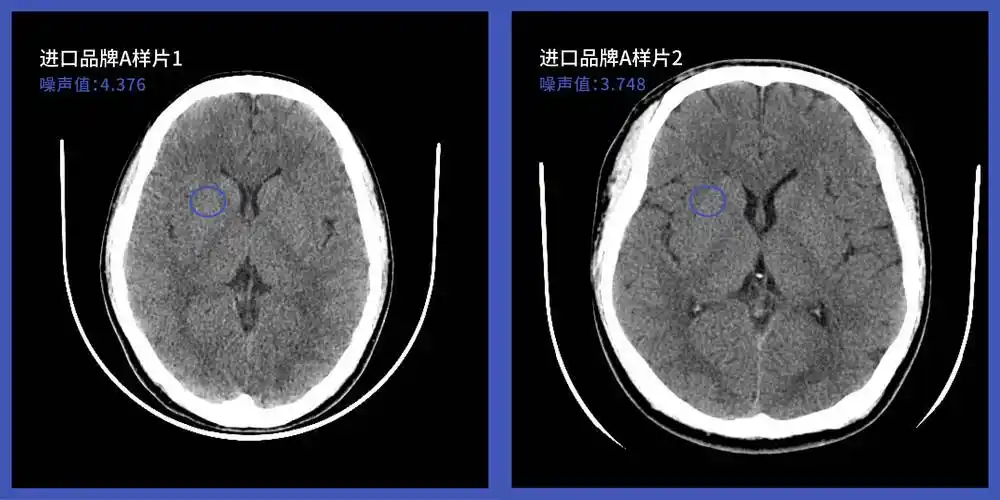

皓月ct头颅图像技术和样片分享